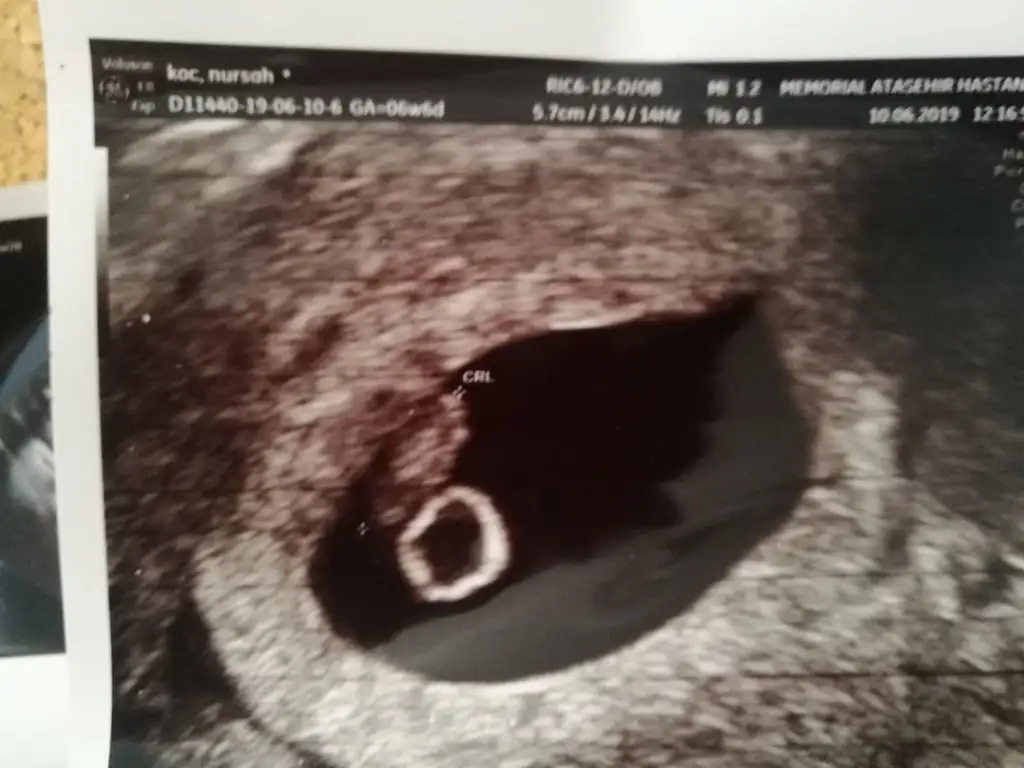

Kız benceEki Görüntüle 2277369 Acaba benim bebişimin Cinsiyeti ne olabilir 8 haftalık Karından

Evet canım sağda duruyor teoriye göre öyleBu teoriye göre bizim kızmı oluyo şimdi arkadaslarkarında usg ile bakıldı